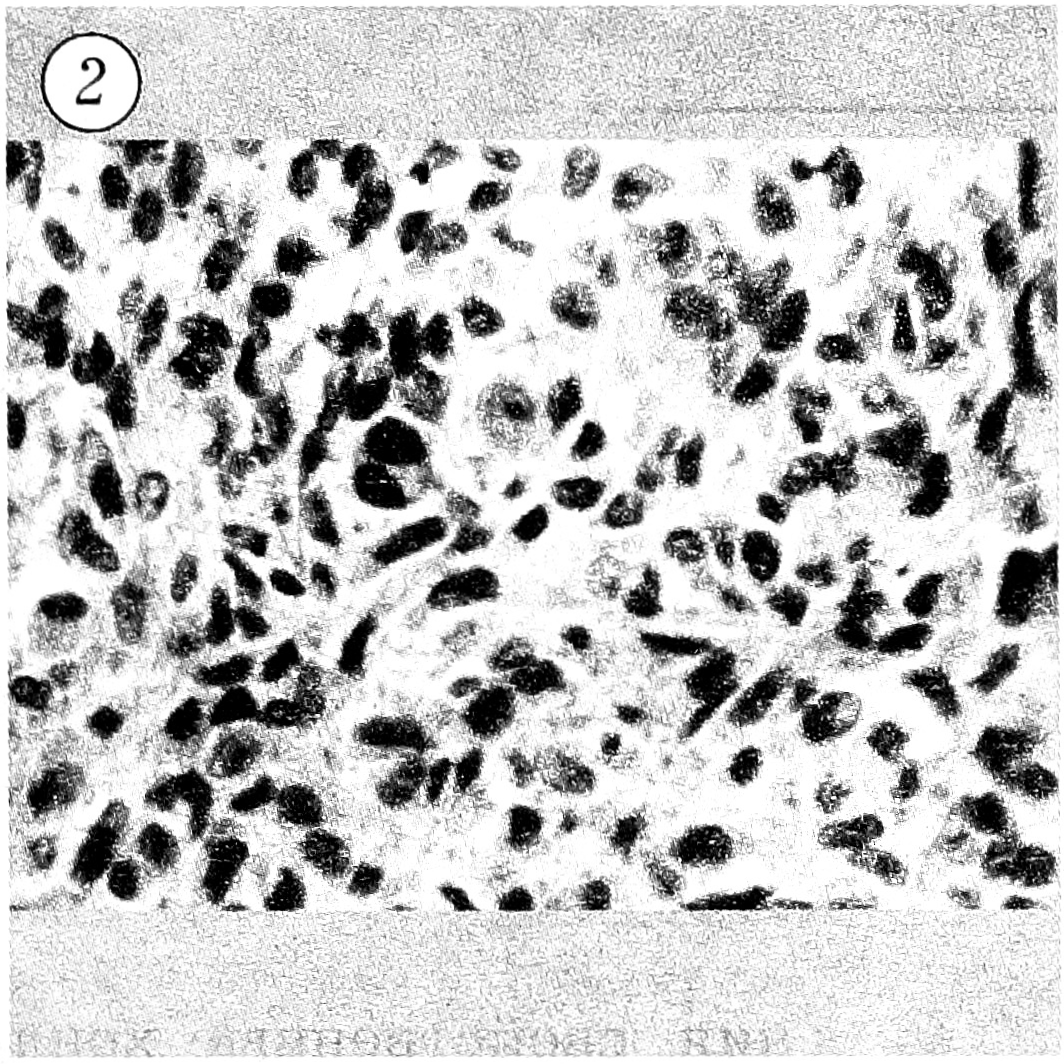

18.08.93 больной оперирован — выполнены околосуставная резекция верхней трети большеберцовой кости вместе с опухолью и прилежащими мягкими тканями единым блоком, электрокоагуляция, замещение образовавшегося дефекта аутотрансплантатом из крыла подвздошной кости. Послеоперационный период протекал без осложнений. При гистологическом исследовании операционного материала обнаружено строение злокачественной хондробластомы. Готовые гистологические препараты консультированы в патологоанатомической лаборатории ЦИТО, диагноз злокачественной хондробластомы подтвержден (рис. 2).

Рис. 2. Гистологическое строение удаленной опухоли: резко выраженный полиморфизм и атипизм клеток при сохранении общего типа строения хондробластомы. Окраска гематоксилином и эозином. Ув. 300.